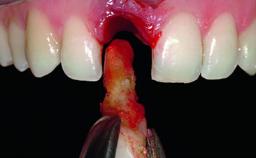

A 30-year-old patient presented at our clinic with a chief complaint of pain in her endodontically treated right maxillary central incisor (tooth 11) with a post-and-core and a fixed single crown. She had a very high lip line, a medium to thin soft-tissue phenotype, and a medium scalloped gingival contour. She also had high esthetic expectations because of her young age and beautiful smile. However, her expectations were realistic and she understood the risks of the treatment. At the initial clinical examination there was a slight mobility of tooth 11; no fistula was observed. The patient also had a single crown on the adjacent tooth 21. Both restorations were old and esthetically deficient. A digital periapical radiograph showed a very small periapical radiolucency, a thick intraradicular post, and no separation between root fragments.